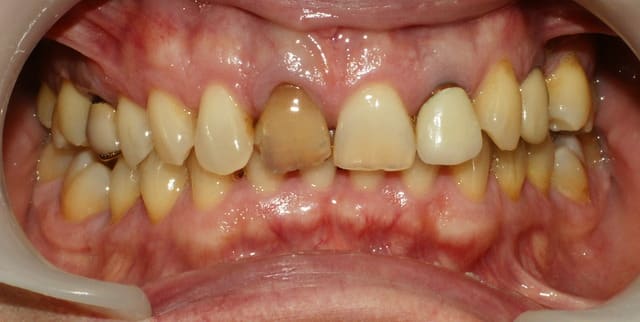

Lâchez vous sur les conseils améliorer ma pratique du composite antérieur, je suis preneur ! en regardant les photos ce matin ... grosse déception ! J'aurais du prendre un peu plus de temps pour le compo, un petit wax up m'a manqué, le montage laisse à désirer ... pas mal de regret au final.

Je ne suis pas d'accord avec ça : ce n'est pas la forme qui est ratée, (un peu mais c'est facile à rectifier), mais surtout le rendu. Il faut utiliser un compo opaque (dentine) et seulement un tout petit peu de translucide par dessus (émail). Ici, tout est trop translucide donc ça tranche avec l'opacité de la dent.

Le résultat est très bien vus les moyens employés, amha c'était un cas d'éclaircissement + facette/couronne, pas de compo direct.

Le deuxième aspect, c'est la différence de translucidité. La reconstitution l'est particulièrement, et la dent naturelle quasiment pas.

Pour la formation, j'ai l'impression que t'en a pas besoin. Il y a dans ton travail un mauvais choix des opacités (voir réflexion de Marc et la juste remarque de chipoudine). l'histoire de la clé palatine en silicone tirée du wax-up peu aider au début, mais avec le temps j'avoue ne plus en faire ou si peu. Il y a aussi un problème de volume: bord libre un poil long, angle distal trop aiguë (élargissant la dent), léger manque en vestibulo-distal sur l'arête distale. Choix des opalescents trop ambre : c'est bien visible en distale.

Le plus important peut être est de bien étudier la photo pré-op pour assimiler la morpho et les caractérisations des dents adjacentes.

Pour ton cas une intégration esthétique parfaite nécessiterait une extension à toutes les imperfections visibles, et l'utilisation de restauration céramique capable de masquer les dyschromies est inévitable.